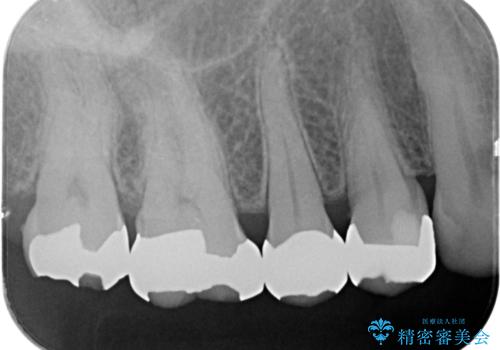

銀の詰め物を外し、欠けたところを覆うように新しい詰め物を作成します。

- 右上5 ゴールドアンレー 77,000円費用は治療当時の料金となります

欠けたところに金属を使用することで、再度欠けてしまうリスクを抑えました。